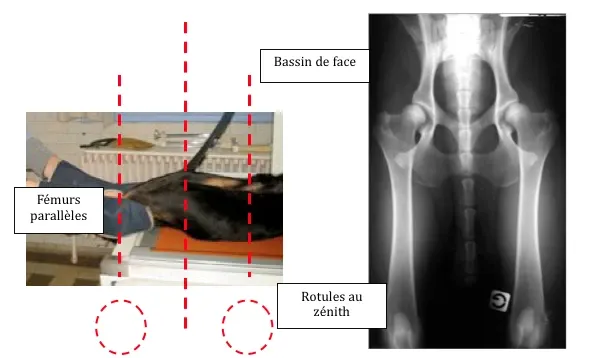

La radio peut être faite par un vétérinaire choisi par le propriétaire, qui certifiera l’identité du chien. Le chien doit être anesthésié (ou sous sédation profonde) pendant la radio et mis dans la position officielle, c’est-à-dire maintenu au niveau du thorax dans une auge, et avec les membres postérieurs maintenus en position relâchée (cf. image ci-dessous).

Un cliché de bonne qualité suppose que : les articulations coxo-fémorales et les grassets sont visibles sur le cliché, les fémurs sont parallèles entre eux et à l’axe du rachis, les rotules sont centrées entre les condyles fémoraux (position dite « au zénith »), le bassin est symétrique (les iliums doivent être de mêmes largeurs et les foramens ovales doivent être parfaitement symétriques).